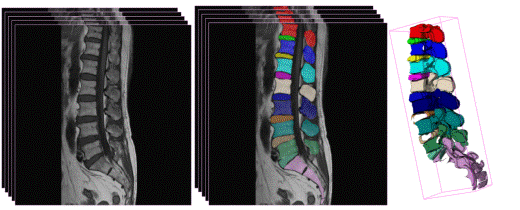

任务:给定一组脊柱T2加权MR三维体数据及其对应的椎体和椎间盘人工标注结果的样本数据,设计方法或者训练模型并开发程序,实现对脊柱T2加权MR三维体数据中椎体和椎间盘的自动分割。

图1. 左:脊柱T2加权MR图像,中:椎体和椎间盘人工标注结果,右:椎体和椎间盘三维可视化显示